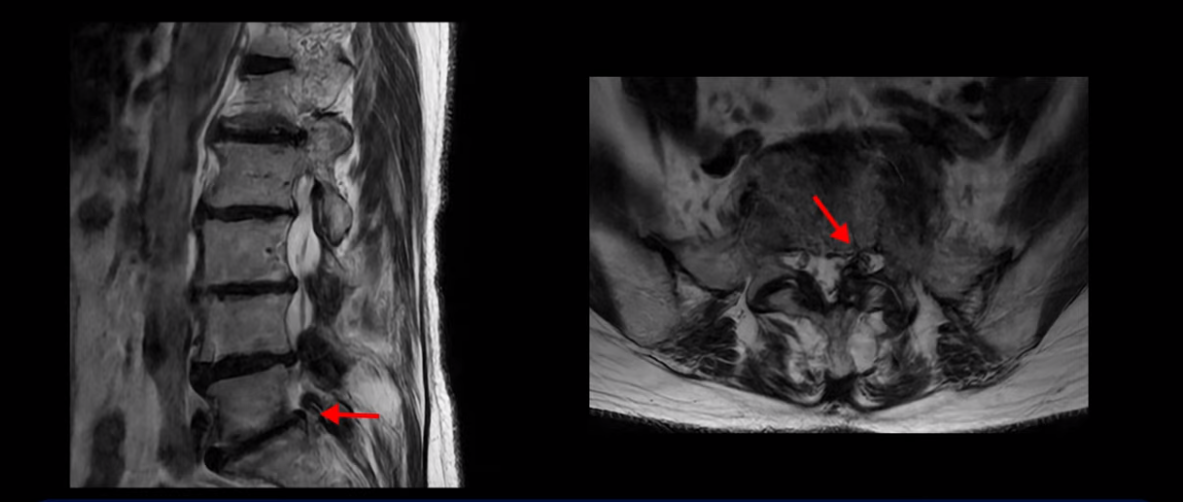

이분 MRI 보시다시피 허리 다섯 마디가 전부 다 퇴행이 심합니다.

특히 4번 5번에는 심한 중심성 협착이 있고,

5번 1번에는 황색인대가 골화되어 왼쪽 신경 나가는 길이 좁아져 있습니다.

그래서 왼쪽 엉덩이와 다리 통증이 더 심합니다. 이렇게 신경 구멍들이 좁아져 있고 신경이 눌리니까 엉덩이와 다리가 너무 저리고 아프고 힘도 빠져서 몇 걸음도 걷기 어려우니까 지팡이를 짚고 저녁에도 아파서 잠을 못 자는 겁니다.